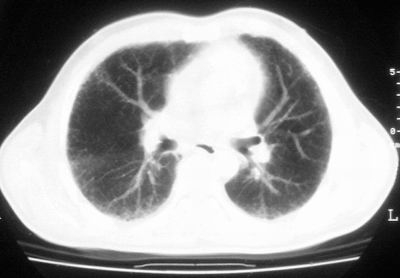

患者,男,44岁,糖尿病4年余,近期消瘦、乏力。化验检查:总胆红素26.33(参考值:5.1-17.2u mol/l),直接胆红素:6.4(参考值:0-4.3u mol/l),谷-丙转氨酶(alt):843(参考值:<40u/l),hbsag(+),抗hbs(-),hbeag(-),抗-hbe(+),抗-hbc(+)。

1\\粟粒性肺结核可能性大,支气管肺泡癌不排除

双肺散在小结节影,考虑粟粒性肺结核.肺窗薄扫会更好看些.

考虑粟粒性肺结核

双肺外侧带胸膜下可见网状阴影,考虑轻度肺间质纤维化。

双肺纹理增强并可见网格状影达外带,考虑双肺感染并轻度间质纤维化

1.双肺急性粟粒型肺结核;2.少量腹水.

肺间质纤维化并肺部感染,结合不能排出,毕竟糖尿病人易合并之,建议结合ppd检查或hrct进一步扫描。